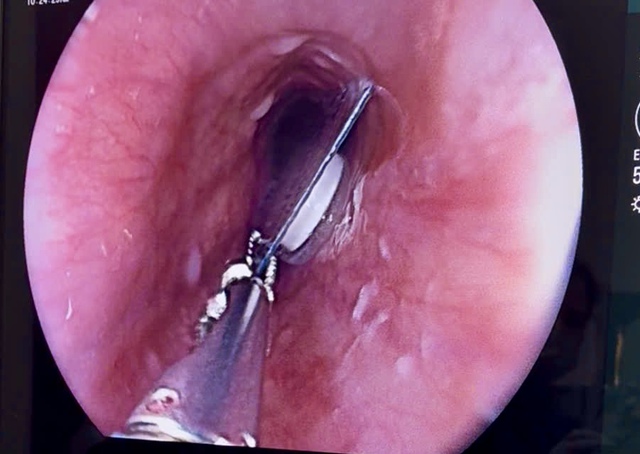

Dị vật là viên thuốc còn nguyên trong bao kẽm nằm trong đường tiêu hóa bệnh nhân.

Qua thăm khám, bác sĩ phát hiện khối dị vật nằm 1/3 phía trên thực quản bệnh nhân. Dị vật là viên thuốc còn nguyên trong bao kẽm, kích thước khoảng 1,5 x 1,5 cm. Đây là loại dị vật sắc cạnh, có nguy cơ gây tổn thương niêm mạc thực quản. Các bác sĩ đã tiến hành nội soi gắp dị vật an toàn.

Các bác sĩ tiến hành nội soi gắp dị vật cho bệnh nhân.